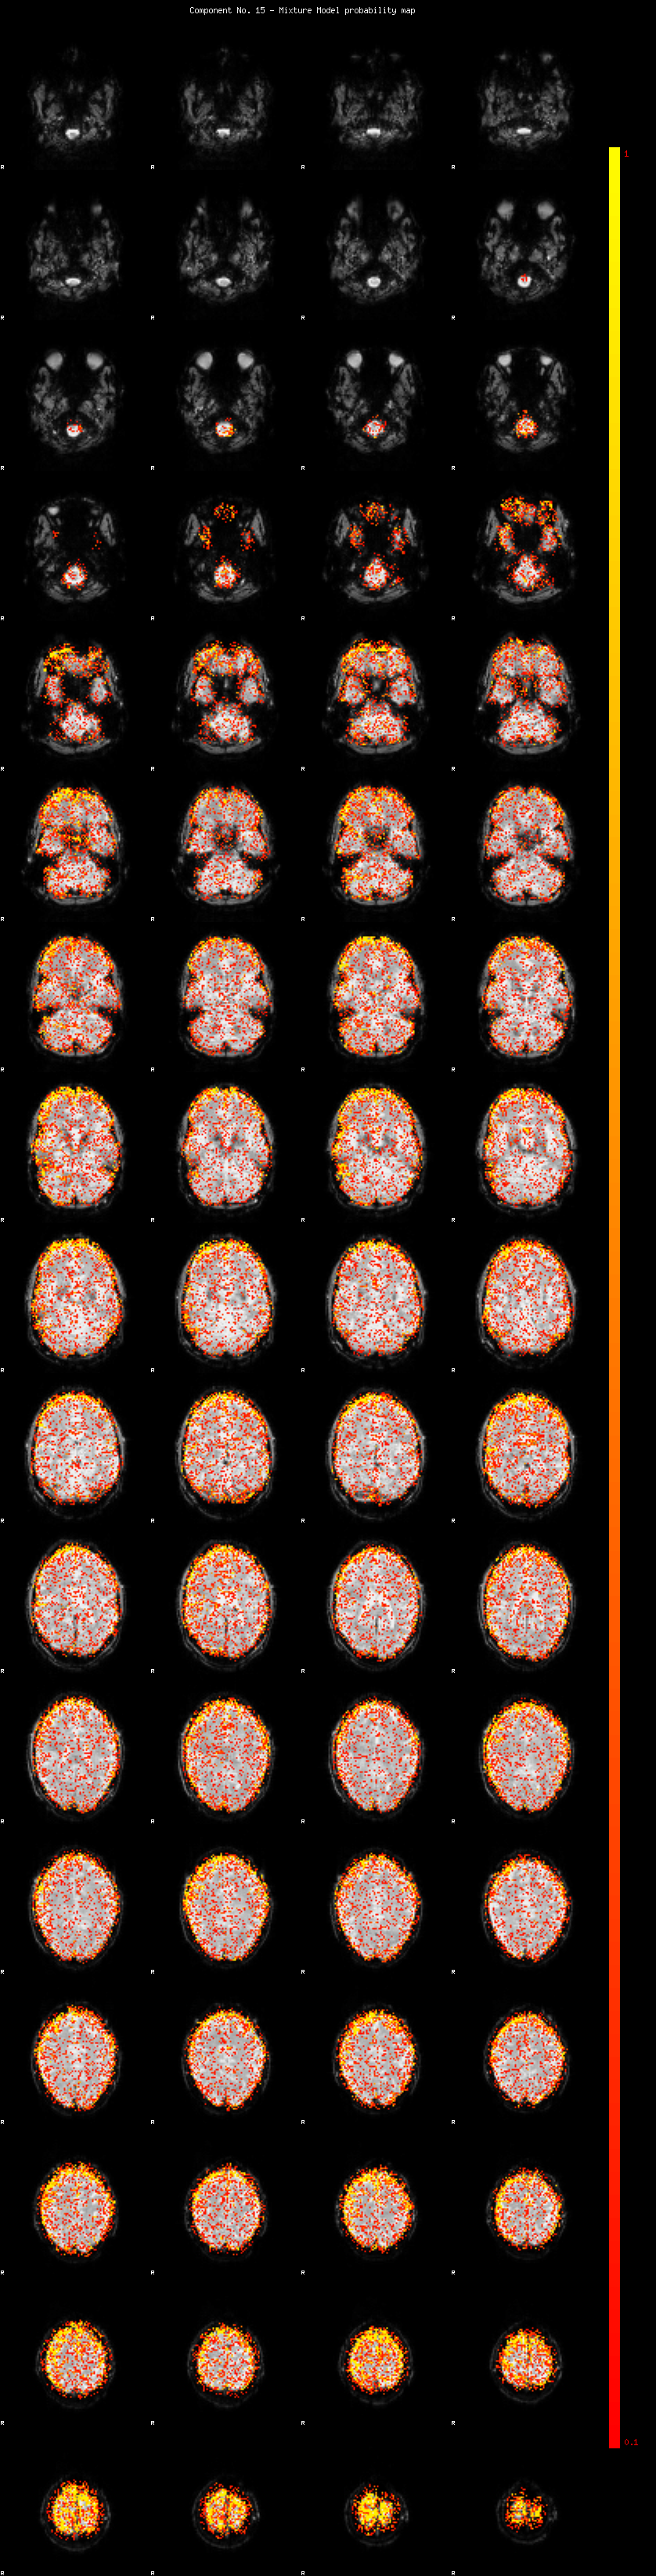

IC_15 Mixture Model fit

Means : 0.000000 2.705384 -2.443181

Vars : 1.000000 2.505798 1.790712

Prop. : 0.859121 0.087894 0.052985